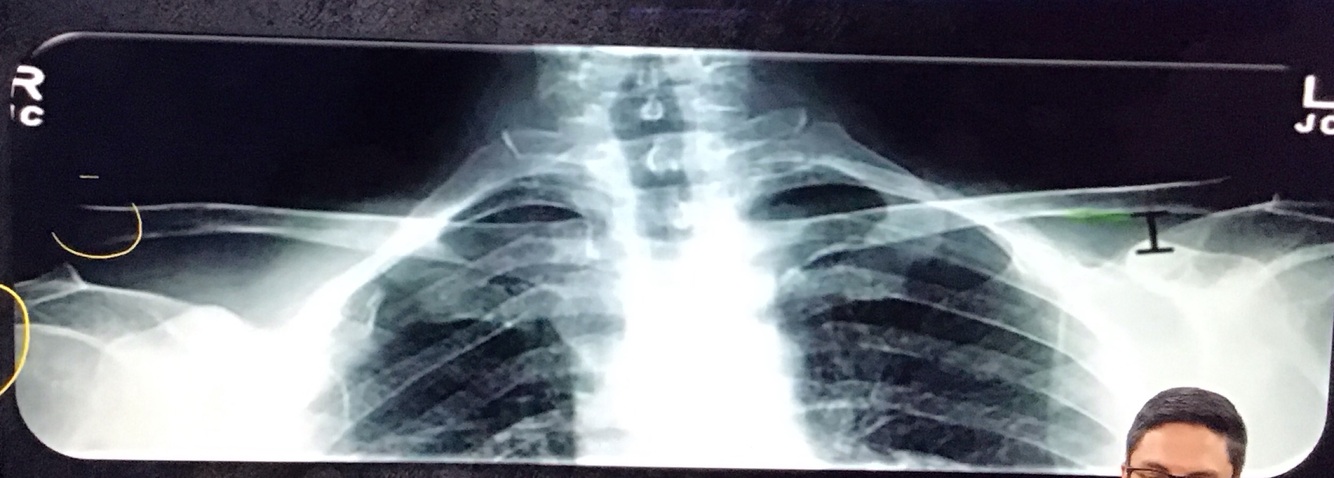

Qual a melhor incidência radiográfica pra avaliar LAC?

A

Zanca

angulação cranial de 10 a 15°

Qual a distância coracoclavicular normal?

11 a 13mm

Qual a distância acromioclavicular normal?

7mm nos homens

8mm nas mulheres